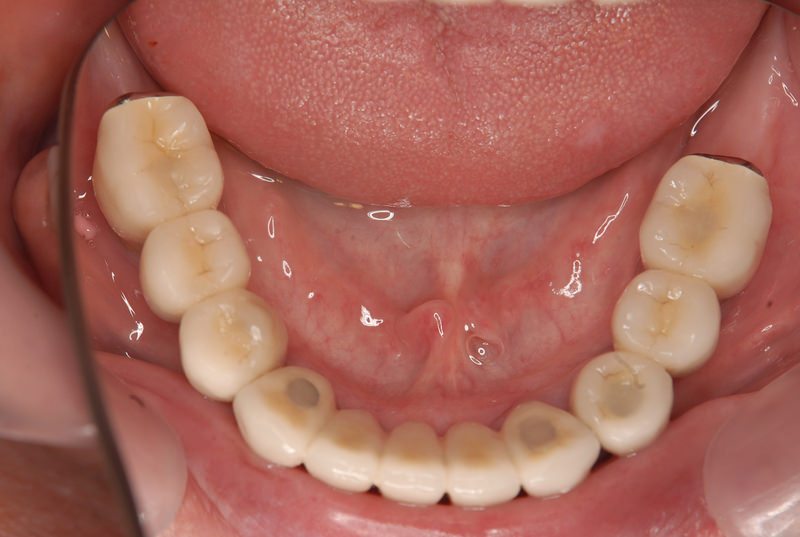

症例2【70代女性】主訴 義歯がわずらわしい・しっかり噛みたい

治療前

治療後(2年経過)

※説明

主訴 上顎のみ部分義歯を使用しているが、入れ歯が煩わしい、固定制のインプラントにして欲しいと来院。

左右上顎第一大臼歯相当は、骨の高さが不足しており、ソケットリフト(骨造成)の必要があり、左右第一小臼歯、第一大臼歯支台のインプラントブリッジを提案。

採血で得られた、CGFメンブレンとAFGブロック(人工骨β‐TCPとAFGを混ぜたブロック)を使用し骨を挙上し、インプラントを埋入。

右下のブリッジも、短根歯で動揺が激しい為に抜歯し、インプラント埋入。

上顎の免荷期間は約4ヶ月、下顎の免荷期間は約2ヶ月を経て、仮歯を装着、リハビリをし、メタルボンド(金属焼付ポーセレン)を装着。

費用 280万(オペ・ソケットリフト・人工骨・採血による濃縮血小板生成・仮歯・最終補綴物まで含む)